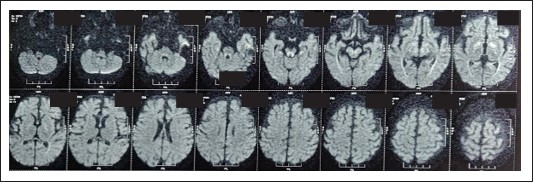

Figure 4: Symmetric DWI high signal (corresponded to hypointensity on ADC) in globus pallidi, PLIC, peritrigonal white matter, optic radiations, brainstem and medial temporal gyri without any abnormal post contrast enhancement.

HRCT revealed consolidations in bilateral upper and lower lung lobes with mild hepatosplenomegaly and borderline cardiomegaly MRI Brain revealed: cerebral atrophy, thinning of corpus callosum and symmetric DWI restriction in globus pallidi, PLIC, peritrigonal white matter, optic radiations, brainstem and medial temporal gyri (which raised the suspicion of INBORN ERROR OF METABOLISM).